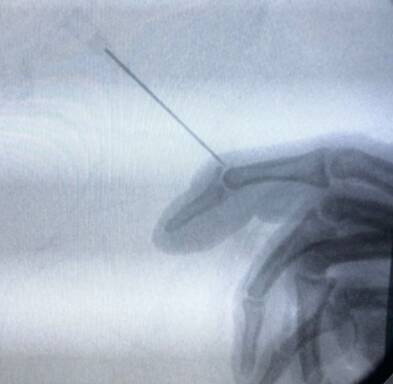

第二枚克氏针